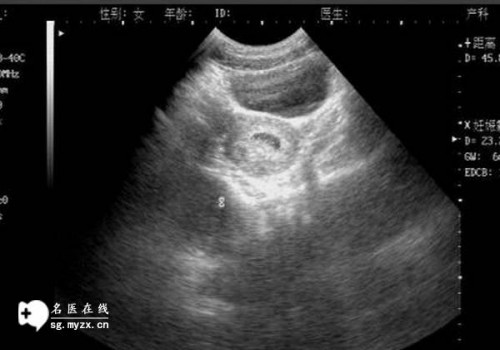

系统超声通常被称为大排畸形,可以在怀孕20-24周之间进行。此时胎儿的四肢已经基本成熟,宫腔比较大,羊水量适当,胎动也比较多。胎儿可以在子宫内自由改变位置,此时超声波可以清楚地看到胎儿各个器官的发育情况。

怀孕 20 周需要进行彩色多普勒超声检查,以了解胎儿的发育情况并排除胎儿畸形。无需憋尿和禁食。如果想进行血液检查,最好空腹进行检查,吃完会影响检测结果。怀孕3个月后,通过彩超检查,没有必要憋尿。孕妇现在20周大,不需要憋尿检查。平时多吃蔬菜水果,不吃辛辣食物。